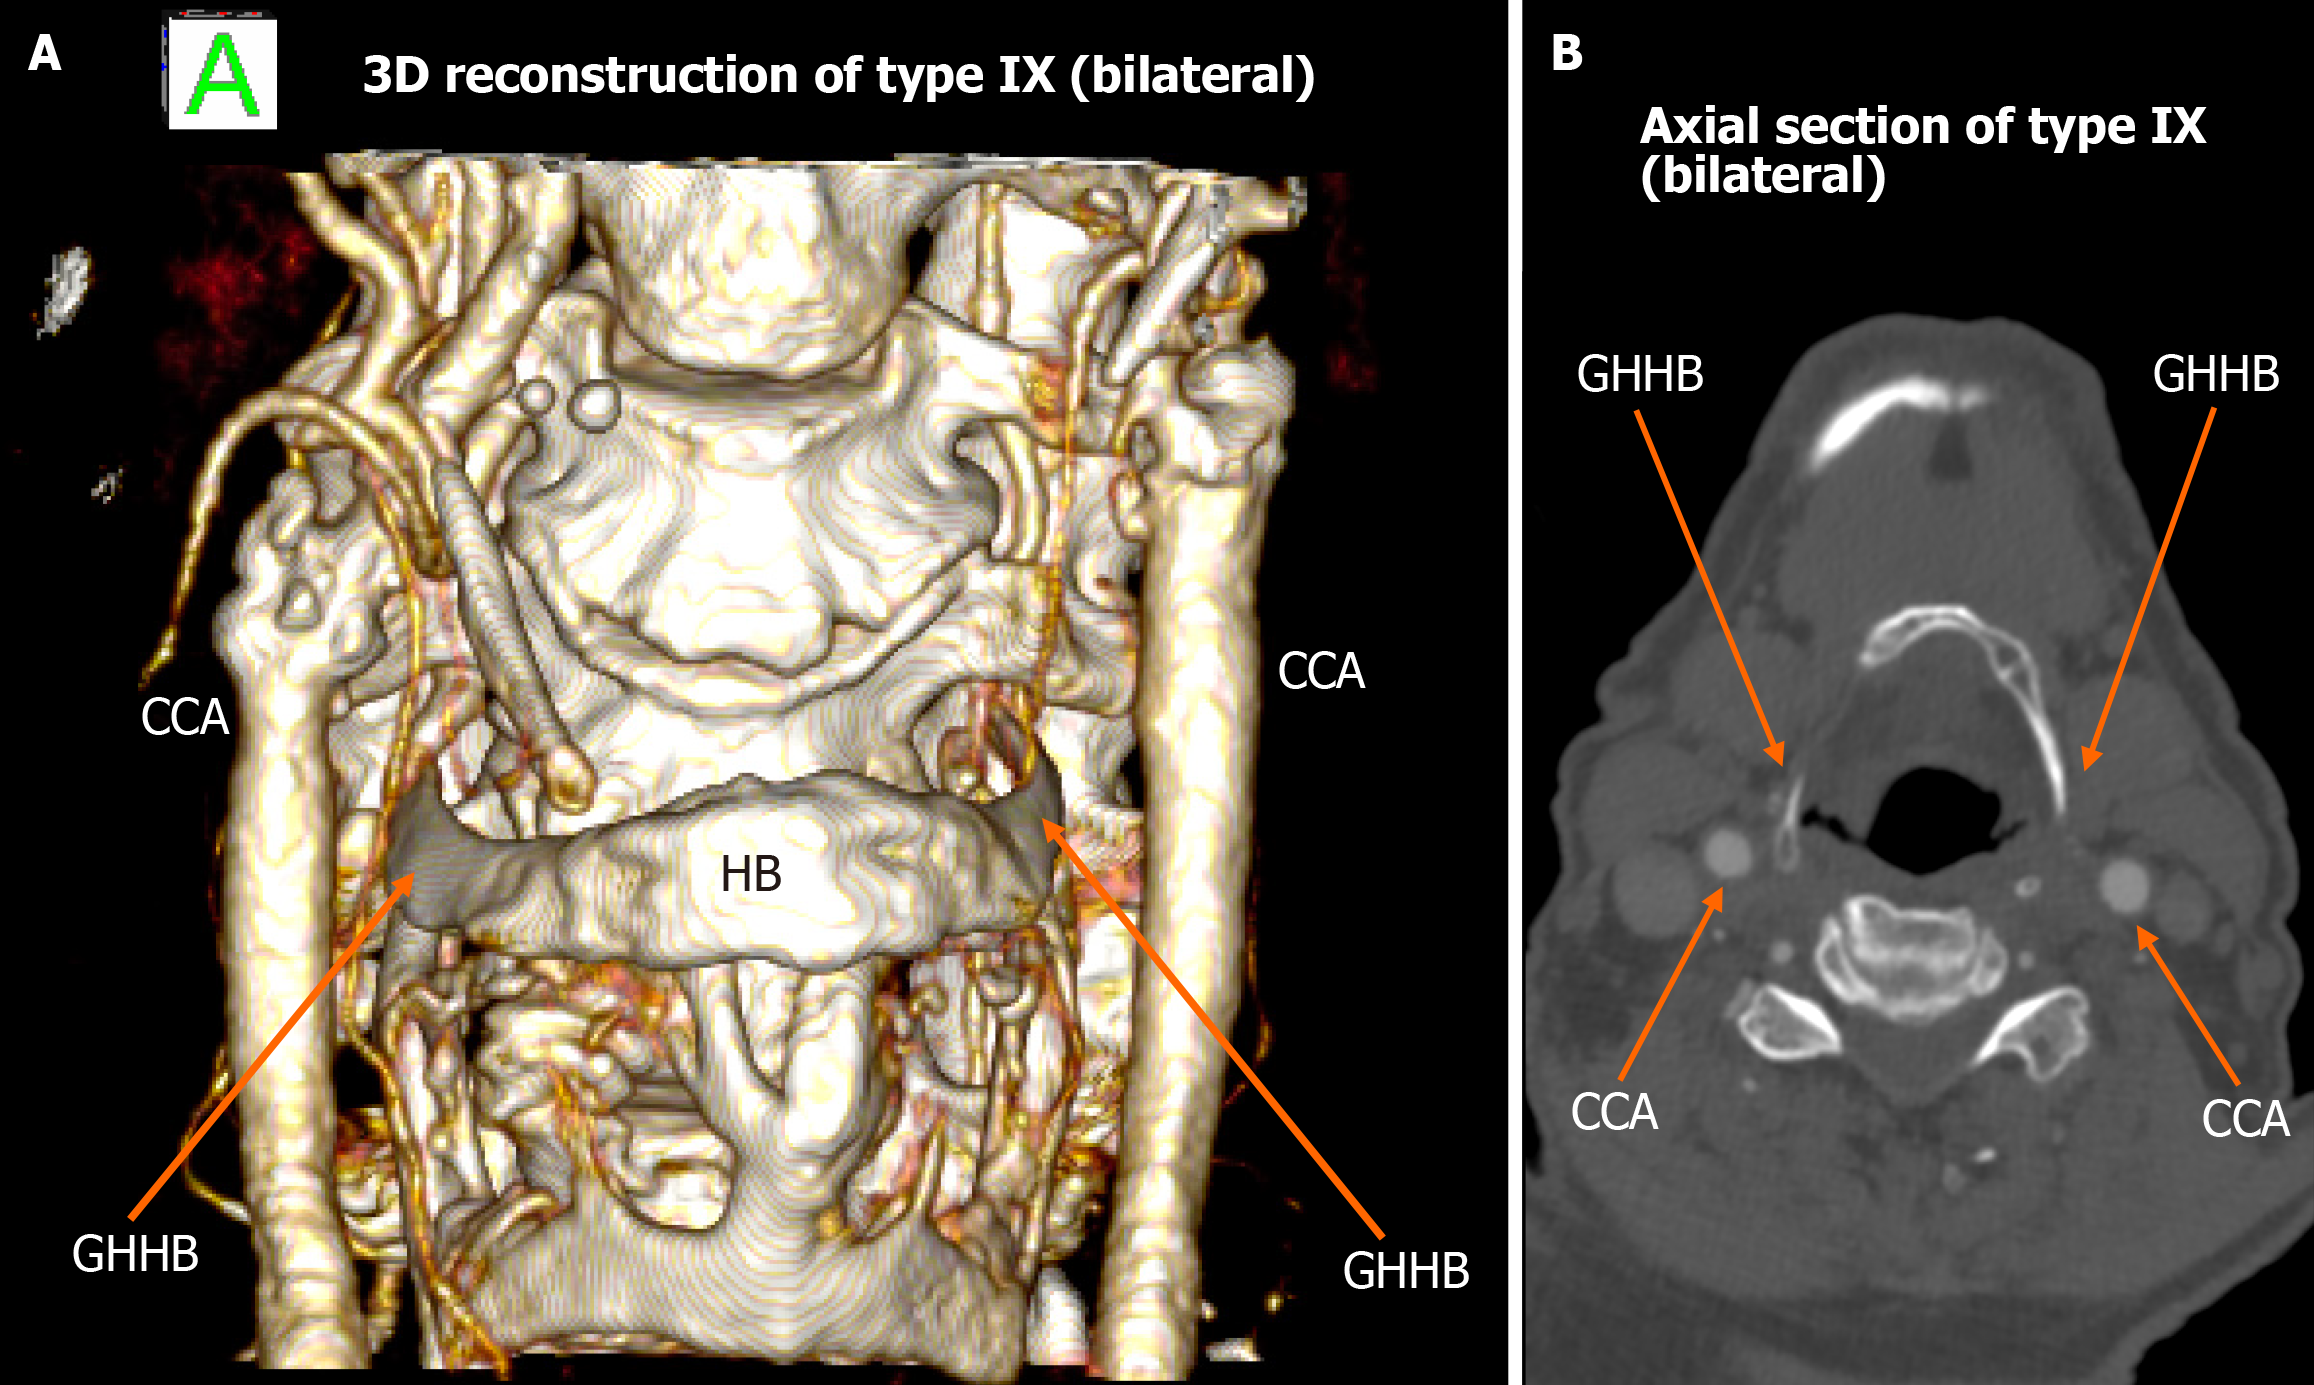

Figure 6 Type IX bilateral configuration.

A: 3D reconstruction shows the internal carotid artery positioned medially to the greater horn of hyoid bone on both sides; B: Axial computed tomography angiography illustrates bilateral type IX anatomy. ICA: Internal carotid artery; GHHB: Greater horn of hyoid bone; HB: Hyoid bone; CCA: Common carotid artery.